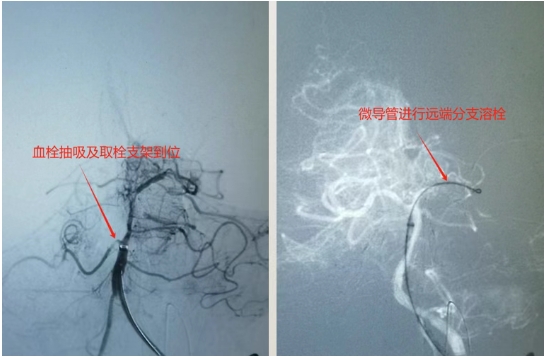

56岁的沙先生,是一名远洋渔船作业人员,工友发现意识不清10余小时。既往甲亢,房颤病史。入院查体深昏迷,刺痛无反应,四肢无活动,双侧病理征阳性,头颅CT提示未见脑内出血。入院诊断:急性基底动脉闭塞,脑干梗塞,房颤。实施术式:脑血管造影,基底动脉机械取栓,脑动脉导管溶栓手术�术中造影可见基底动脉闭塞,考虑血栓脱落导致。不及时开通,致死的可能性大�进一步采取支架及取栓导管抽吸取栓,微导管动脉内溶栓手术方式,及时开通了基底动脉主干及主要分支�患者术后刺痛反应较前改善,浅昏迷。经气管切开,脱水,改善脑循环等积极治疗后,病情稳定后转回当地樱花动�

脑动脉取栓术是指使用微创介入技术,在大腿根部的股动脉进行穿刺,或经桡动脉等入路,借助取栓支架、抽吸导管、球囊等材料,将闭塞部位的血栓取出,对闭塞的脑血管进行再通,以最快的速度开通闭塞的脑血管,恢复脑血流,挽救处于缺血过程的脑组织、脑细胞�